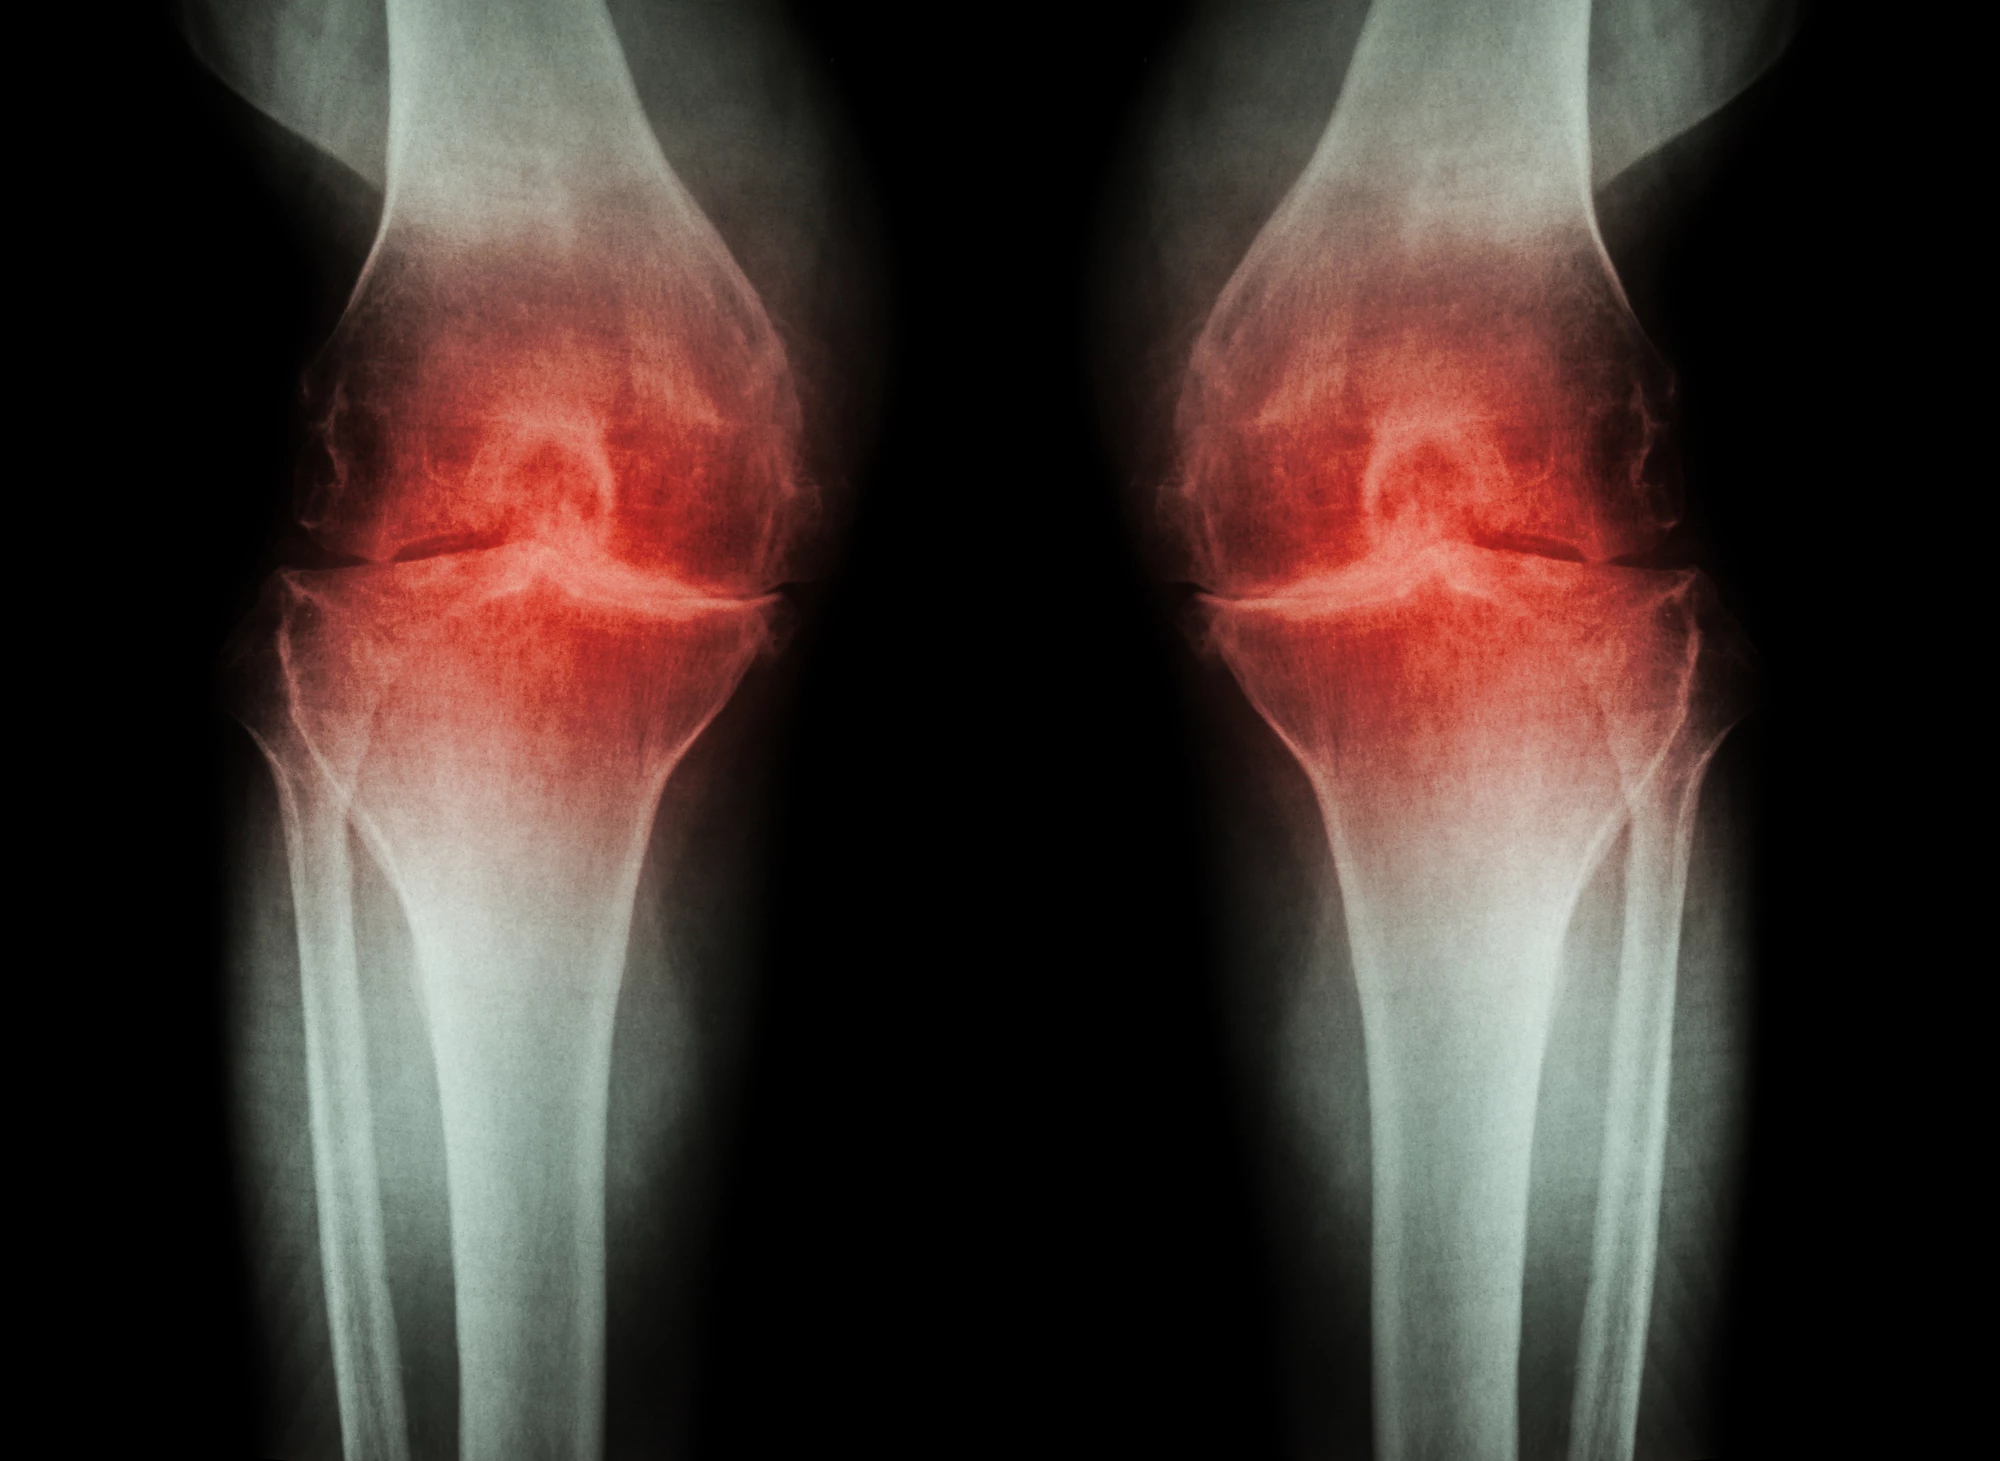

Osteoarthritis can be a debilitating disease, rendering regular movements painful. Researchers have now identified a signaling pathway that transmits this pain, with a study in mice finding that normal limb use returned after this pathway was blocked. The work could lead to new pain treatments for patients with osteoarthritis.

The disease begins as the cartilage in joints wears away, causing pain as bones increasingly rub against each other. Pain can be managed using over-the-counter medication or lifestyle changes, but can remain a problem as the disease progresses. To find better long-term drugs to manage chronic pain, scientists have been investigating the molecular pathways that communicate pain to the brain.